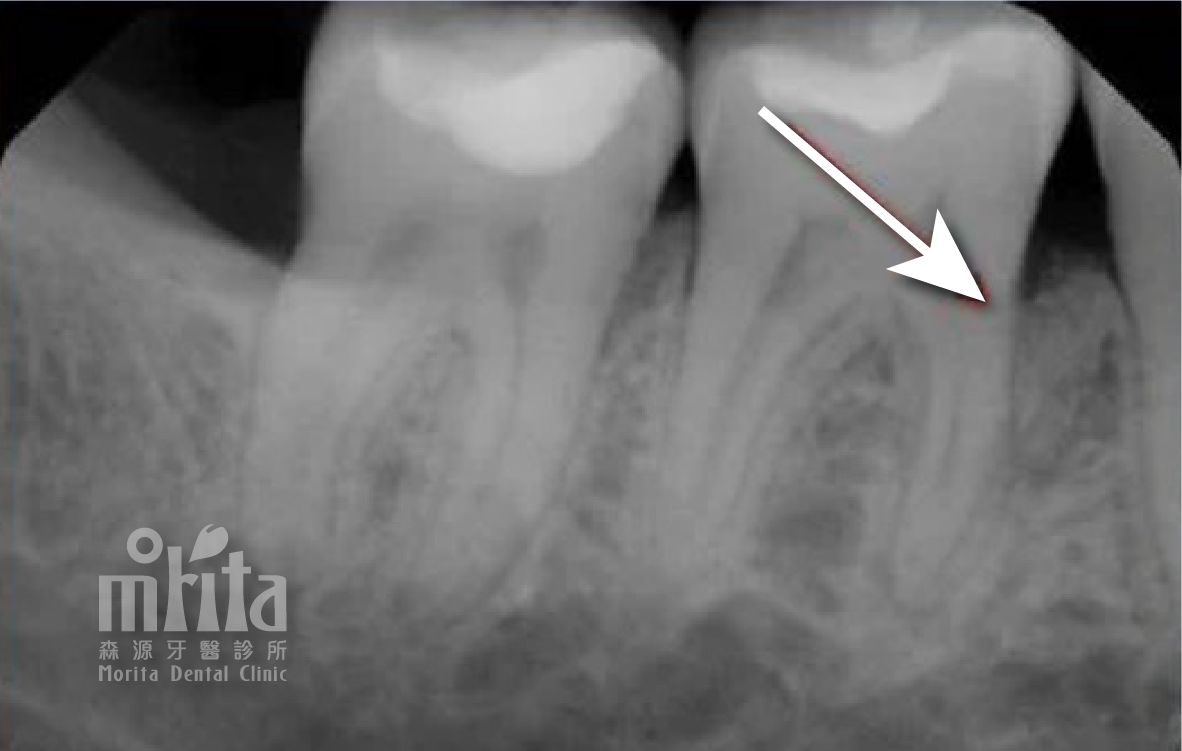

牙冠增長術 Crown Lengthening Procedure

當牙齒因齲齒或是外傷斷裂,造成牙齒的結構脆弱與長度過短時,我們就可以透過牙冠增長術來增加牙齒露出的長度,才能進行齲齒治療,並能增加未來製作假牙的穩定度。

牙冠增長術 術前術後